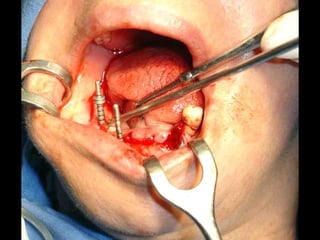

Sutura de colgajosque cubren la estructura, dejando los postes bien visibles.

Colocación de laprótesis dentaria.